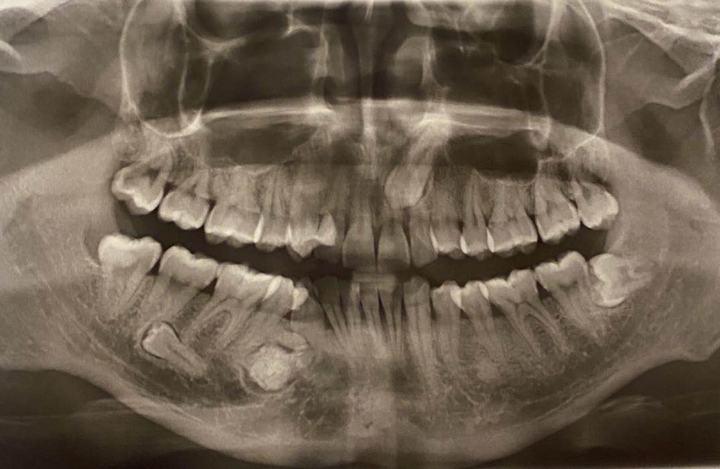

双侧下颌骨牙骨质瘤(多发性)